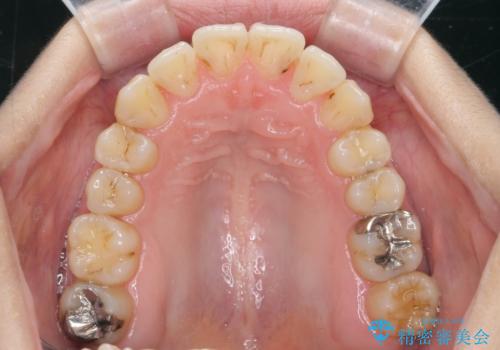

前歯のがたつき すれ違い咬合のマウスピース矯正治療

- 前歯のがたつきや歯の角度、矯正治療を希望され来院されました。

仕事の都合で、ワイヤー矯正を行うことが難しくマウスピース矯正であれば可能、という希望でした。

下顎が前にある咬合関係を可及的に咬合移動で改善し、IPR、下顎3前歯の仕上げで行うマウスピース矯正を計画します。